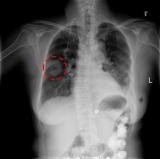

山东医专附院影像科引进日立数字化移动式X射线机开始为患者保驾护航

2020年5月20日下午14:06 山东医专附院影像科接到呼吸内科李德瑞、韩柳两位主任及护士长张克芹的电话,有一位年老体弱的患者,体质较差,需要长期吸氧,无法到影像科进行检查,需要进行床边摄片。 2020-05-22 产业应用